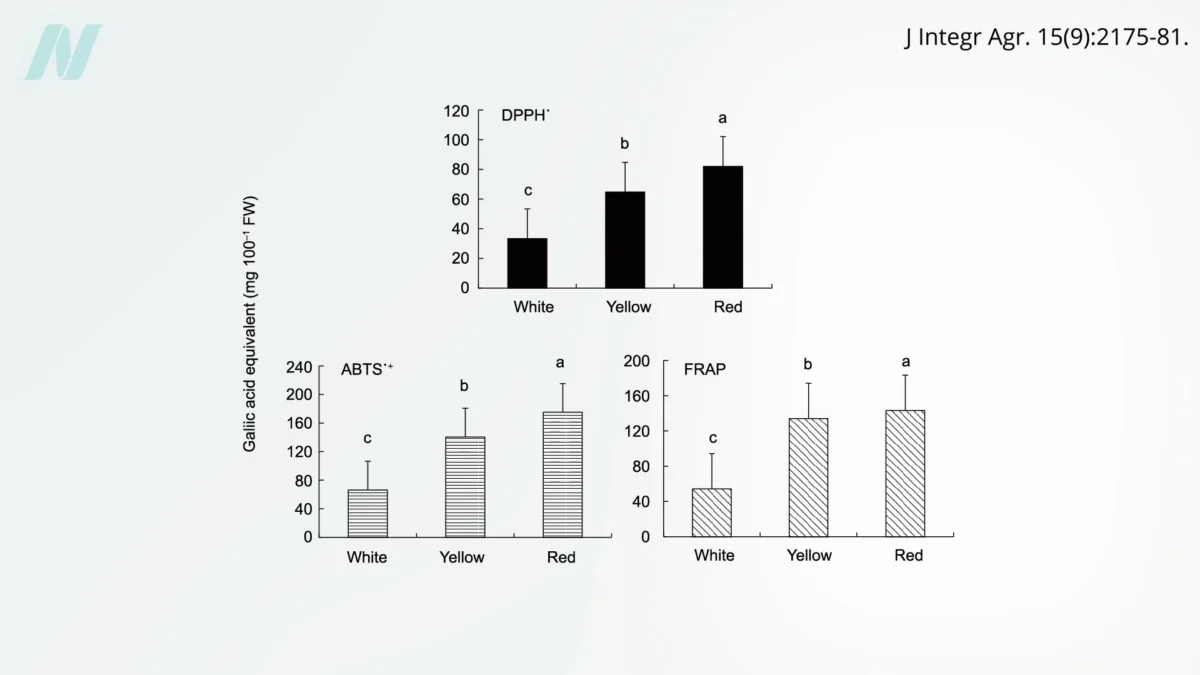

Onions: Unpacking the Evidence from Randomized Human Trials for Health Benefits

Onions, a staple in kitchens worldwide and a cornerstone of countless culinary traditions, have long been lauded for their potential health-promoting properties. While anecdotal evidence and traditional medicine have often…